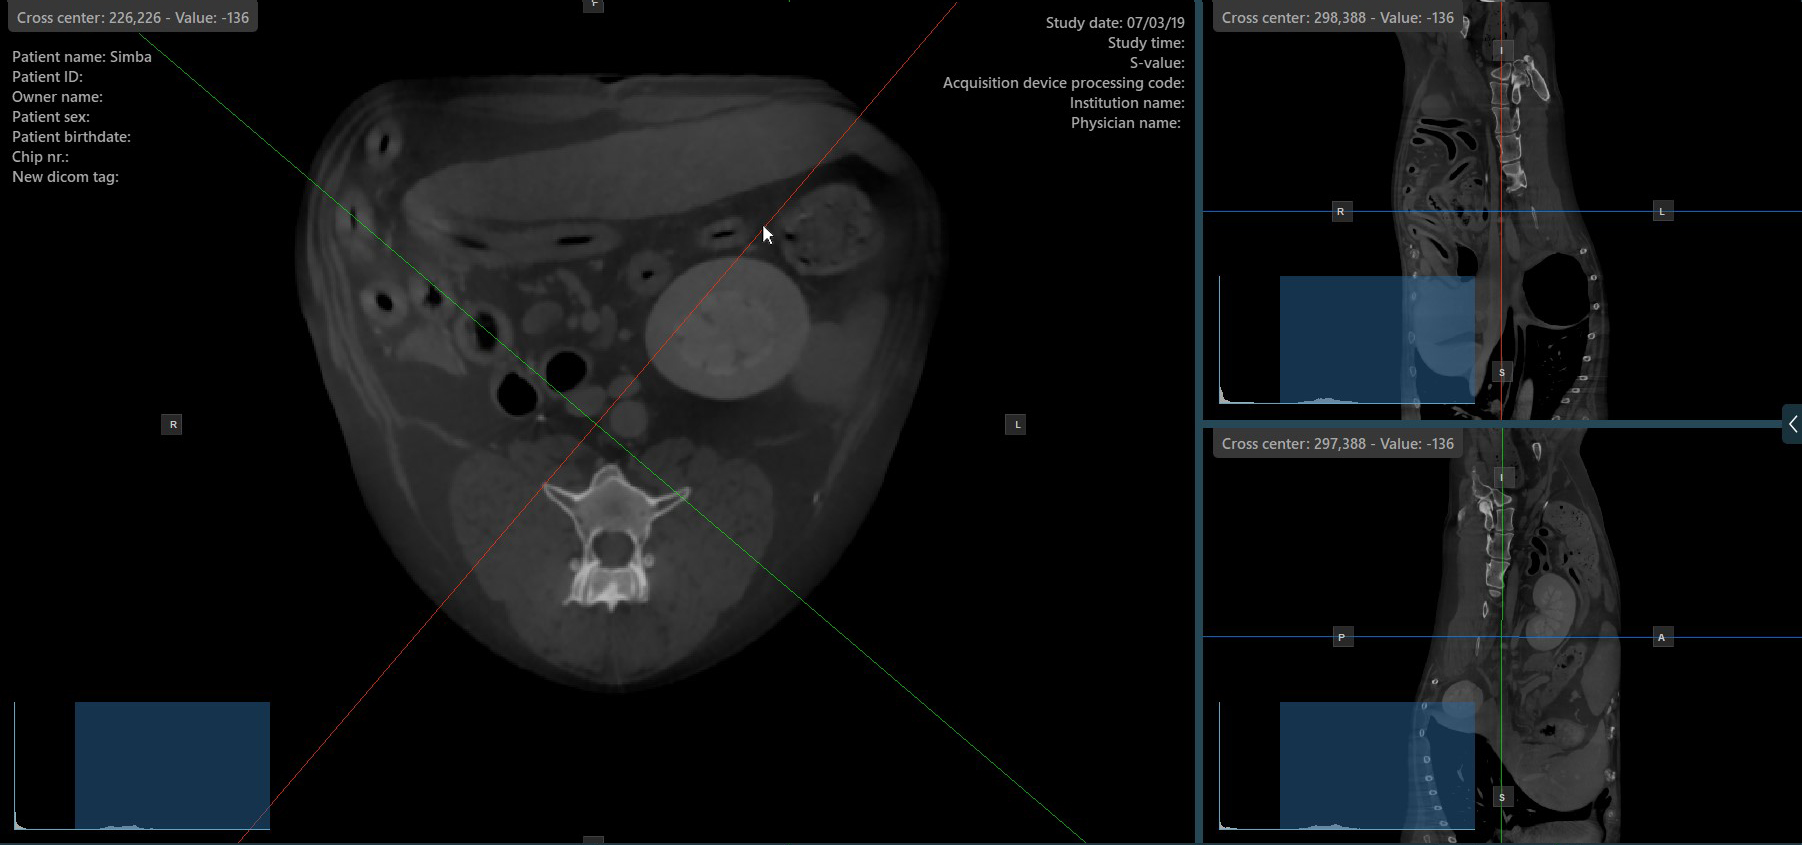

Change Slicer Rotation¶

Altering the rotation of a slicer will change the orientation of the corresponding image planes. Individual slicers can be selected by using the Select Item (Default) tool, assigned to the right mouse button by default.

Once the specific slicer is selected, drag the slicer in the desired direction to rotate it. The corresponding image plane’s orientation changes accordingly.

By default, each slicer can be rotated separately. The corresponding icon in the left toolbar of the CT Viewer will be deselected when the slicers are rotated individually.

Press the Perpendicular Slicers icon in the left toolbar to activate simultaneous rotation of the slicers. Regardless of their previous orientation, the slicers are repositioned to be perpendicular to each other.

Toggle the Perpendicular Slicers option to switch the active mode of the slicers at any time, or choose one of the Tools -> Perpendicular Slicers or Tools -> Separate Slicers options from the CT Viewer menu.